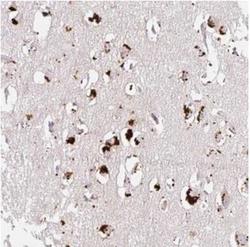

- Main image

- Experimental details

- Immunohistochemistry-Paraffin: CLEC3A Antibody [NBP2-30595] - Staining of human cerebral cortex shows strong cytoplasmic positivity, with a granular pattern in neuronal cells.